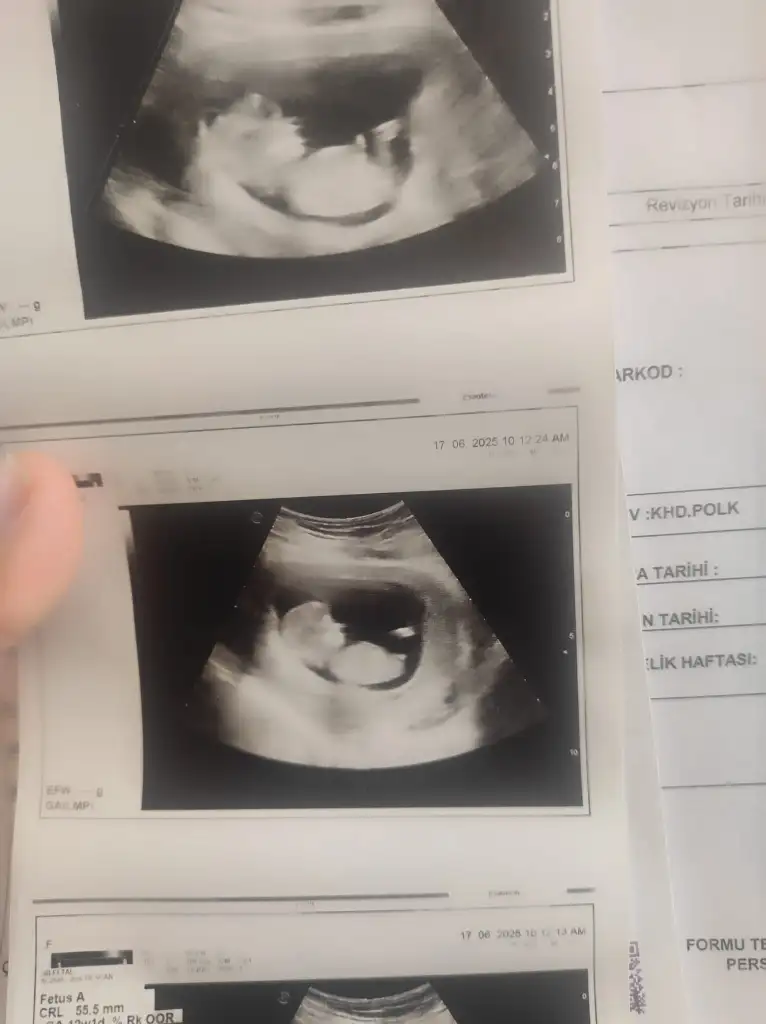

Cinsiyet tahmini yapabilir misiniz? :)